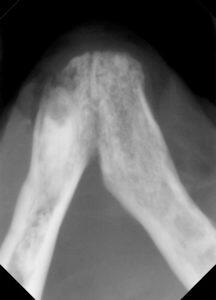

レントゲンで確認できる残根を抜歯し、下顎犬歯はより深い場所で切除を実施しました。

歯科処置は、術中に抜歯が必要か、そしてどの様に抜歯をするか判断するために、歯科レントゲン検査が必要になります。

また、術後にもレントゲン撮影をし、抜歯後の状態を評価しなければなりません。